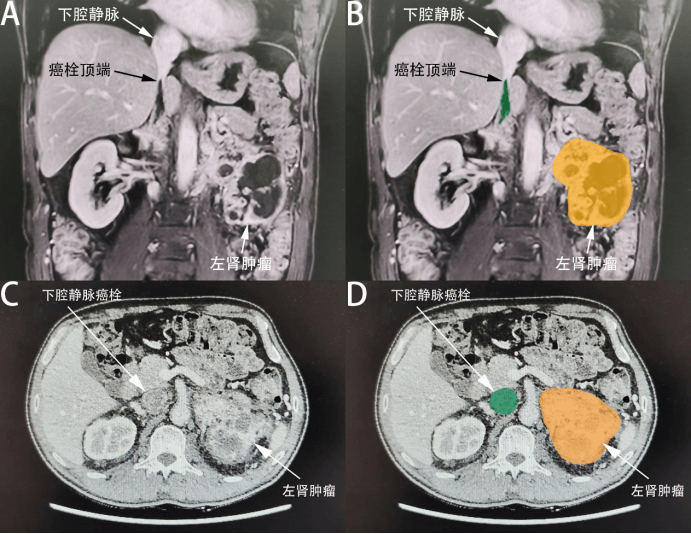

52岁的孙先生怎么也没想到,一次普通的腰痛竟暗藏致命危机。一年多前,他开始出现左侧腰痛,因无肉眼血尿等症状,自行服用止痛药后缓解,便未重视。直到2024年 11 月,他在当地医院体检发现肌酐值飙升至 216.4μmol/L(正常范围约53-106μmol/L),进一步 CT 检查揭示了惊人真相:左肾有一个约10.5×8.7cm的巨大肿块,癌栓已侵入左肾静脉及下腔静脉,甚至突破膈肌,达到肾癌合并静脉癌栓最严重的 MayoIV级(癌栓顶端超过肝静脉开口)。此外,肝脏和肾上腺还发现可疑转移结节,病情岌岌可危。

术前增强磁共振及CT影像

泌尿外科团队评估后认为,孙先生的癌栓位置高、体积大,直接手术风险极高。于是决定先采用靶向药物培唑帕尼进行新辅助治疗,为手术创造条件。经过4个月的治疗,奇迹逐渐显现:左肾肿瘤缩小至约9.2×8.0cm,下腔静脉癌栓顶端退缩到肝静脉开口下方(Mayo分级降为接近III级),肝脏转移结节消失,肌酐值也有所下降。这些变化意味着癌栓从 “不可切除” 转为 “可能切除”,手术窗口终于打开。